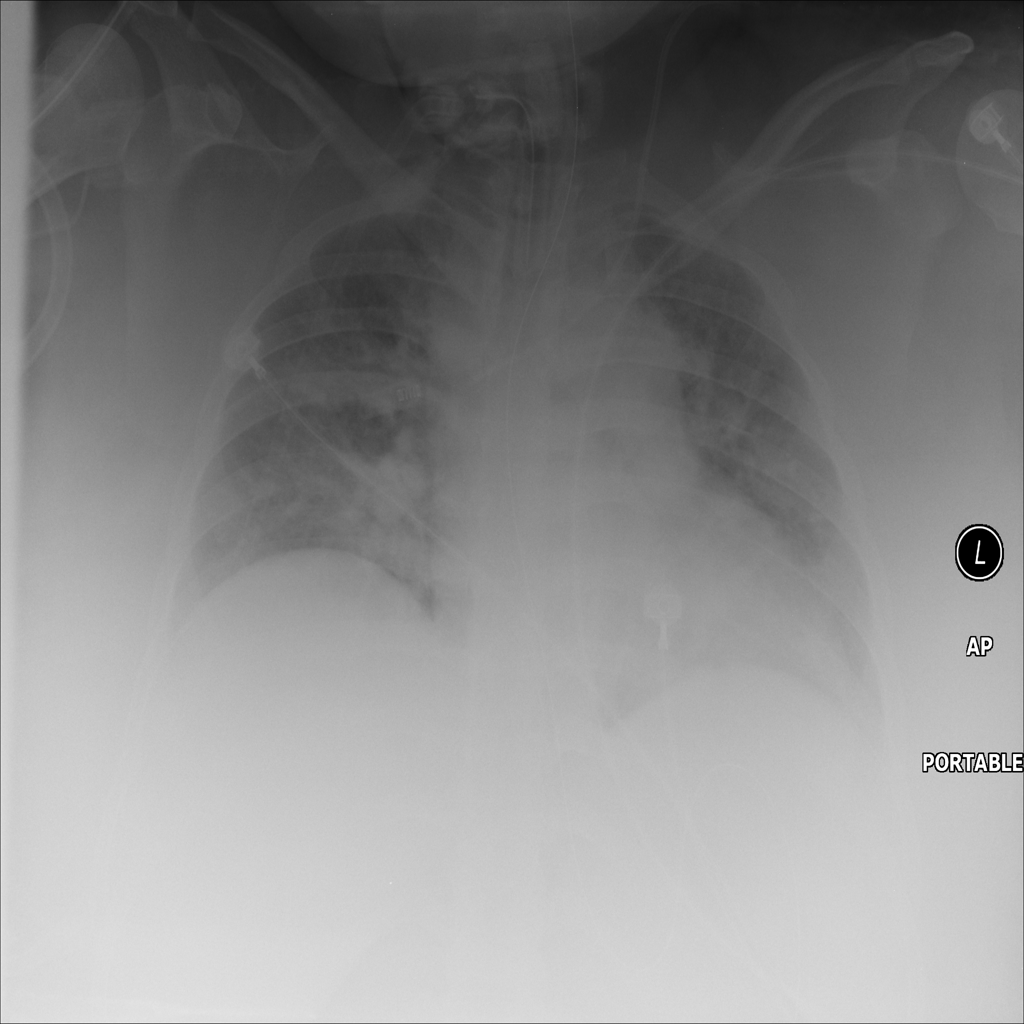

PAT-24D9 · IMG-006Edema

PAT-24D9 · IMG-006

AP